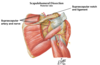

Muscles of the rotator cuff

Supraspinatus

Infraspinatus

Teres minor

Subscapularis

The quadrilateral or quadrangular space.

Formed by three muscles and the medial border of the humerus.

The axillary nerve and the posterior circumflex vessels (artery and vein) forming the neurovascular bundle pass through this space to reach their destination.

The suprascapular nerve passes below the ligament, while the suprascapular artery and vein pass above.